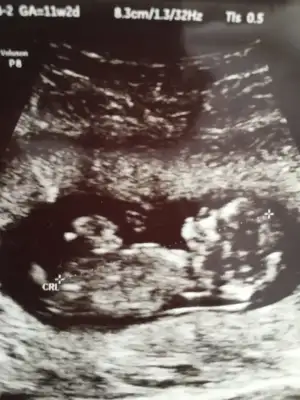

dr soylemeden siz gorun genital nub teorisi ( bebegin cinsiyeti)

Canım emin değilim en iyi 11 12 13 haftalar olmalı dedim yinede USG ile uğraşıp cizeyim gördüğüm nub ise 🙈

Bu nub değil artık çizdigim organı oluşmuş oluyor yanılmış olabilirim bu haftalar benim alanım degil 🙈 gördüğüm pipi olmayabilir ☺️Eki Görüntüle 2770911